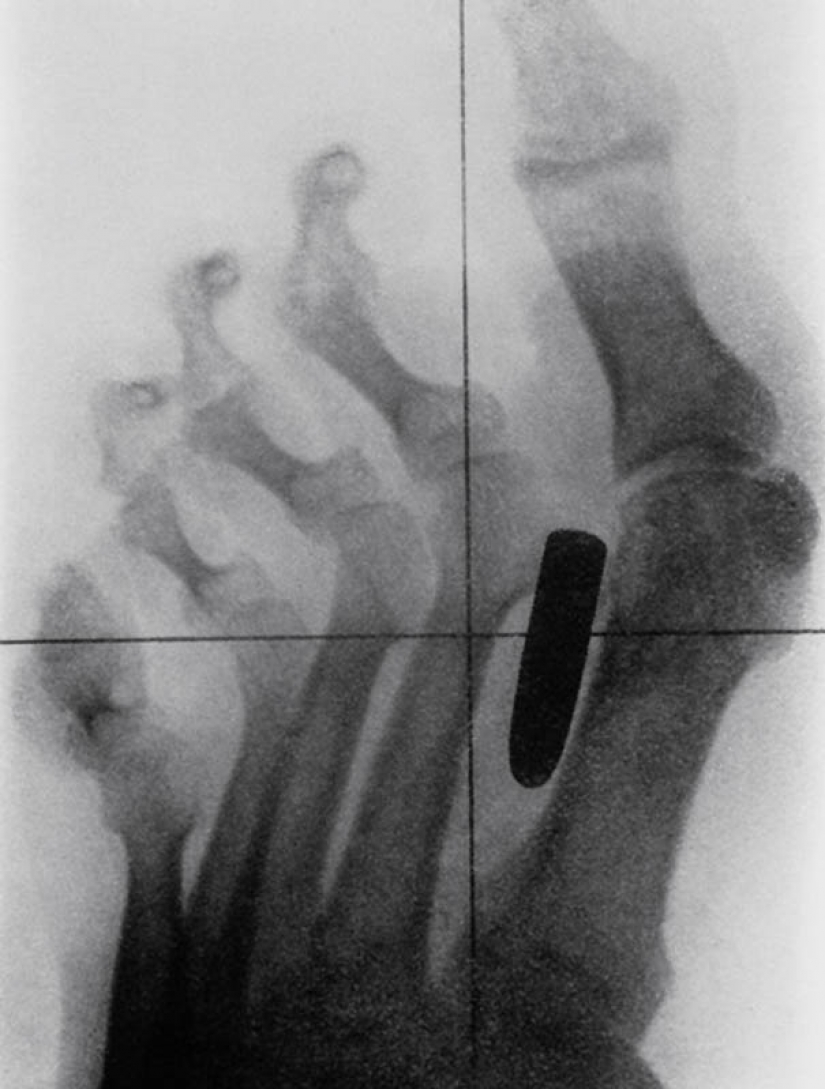

4. The nail in the bones of the index and middle fingers of adult men.